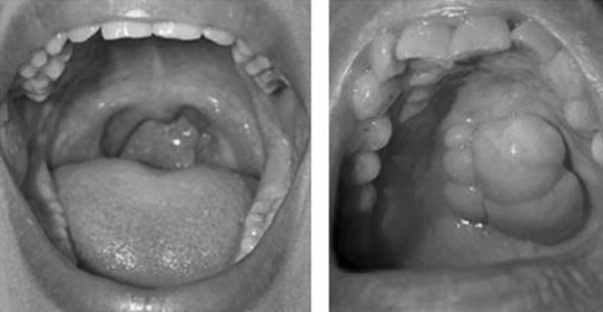

Vùng tổn thương loét, chảy máu lâu ngày không khỏi trong miệng là dấu hiệu cảnh báo ung thư khoang miệng.

Ung thư khoang miệng có thể biểu hiện bằng nhiều triệu chứng khác nhau. Trong giai đoạn đầu, các dấu hiệu thường khá mơ hồ nên dễ bị bỏ qua.

• Vết loét ở môi hoặc trong miệng lâu ngày không lành. Xuất hiện khối u hoặc vùng mô bất thường trong khoang miệng